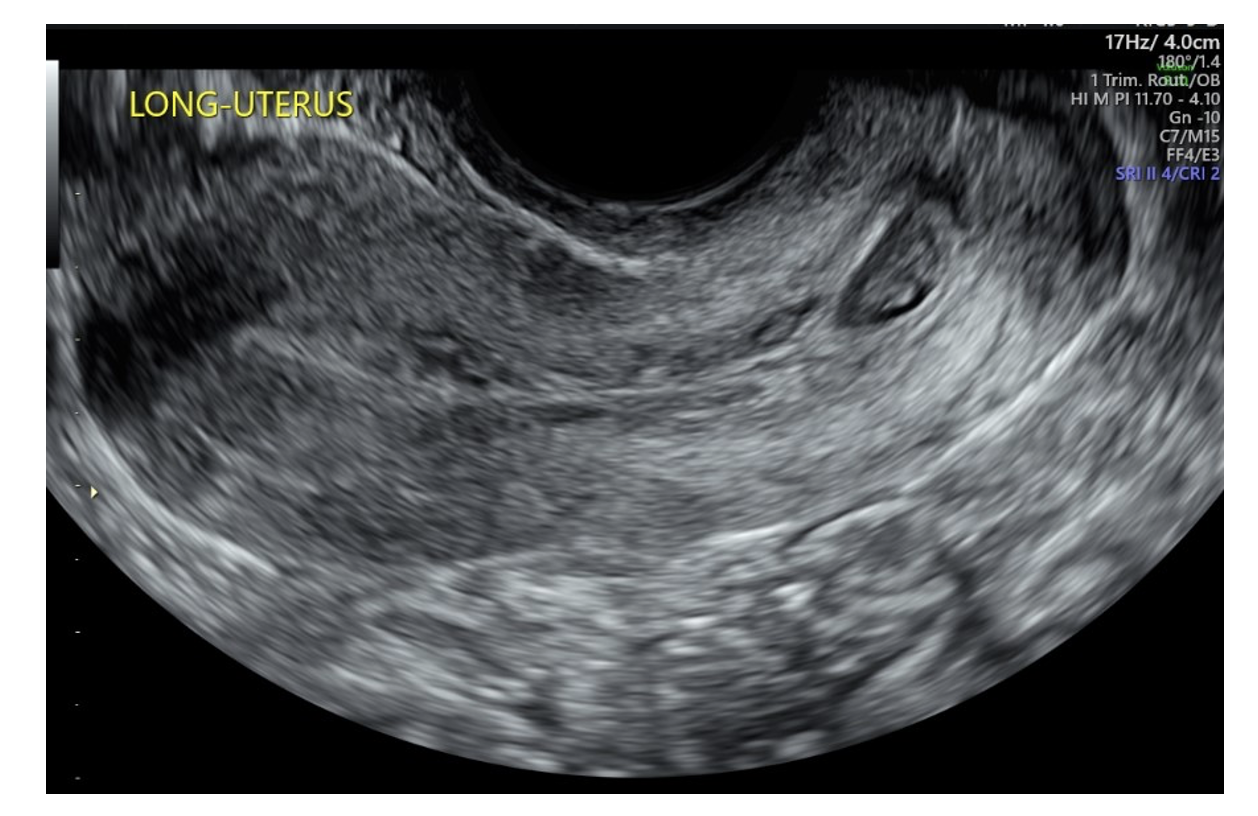

A 35-year-old woman (gravida 1, para 0) was found during an initial first trimester ultrasound to have a CP at approximately 10 weeks’ gestation (Figure 4) with fetal cardiac activity. She had no bleeding or pain at the time of presentation and β-hCG was 80,931.3 mIU/mL. Management options were discussed with the patient, including D&C with VIR support, systemic methotrexate, intra-sac methotrexate, and gravid hysterectomy. The patient elected to proceed with D&C with VIR support as she desired future fertility.